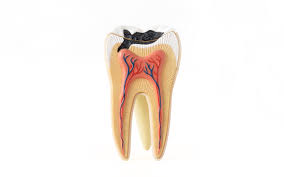

사랑니는 마지막 어금니로, 대부분 10대 후반~20대 초반에 올라오기 시작합니다. 문제는 이 치아가 제대로 자리를 잡지 못하고 옆 치아를 밀거나 잇몸 안쪽에 비스듬히 숨어 자라면서 통증과 염증을 일으킨다는 점입니다.

- 잇몸 염증: 사랑니 주변에 음식물 찌꺼기가 쌓여 세균 번식이 생기며, 심하면 고름이 생길 수도 있습니다.